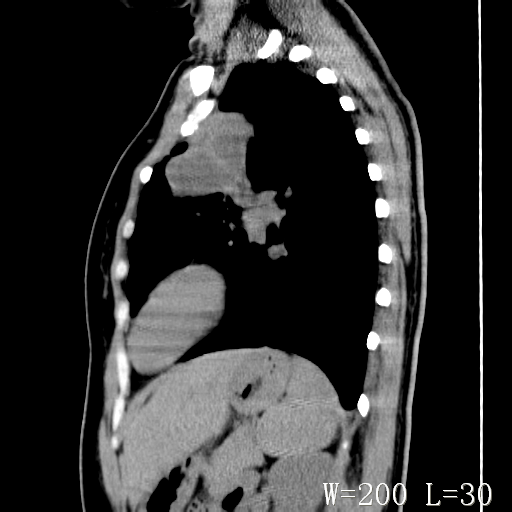

标题: CT27017:1、肺结核?2、永存左上腔静脉。 [打印本页]

标题: CT27017:1、肺结核?2、永存左上腔静脉。

女,32岁,自述肺结核治疗多年复查。

1)考虑左肺上叶肺脓肿,节段性肺不张。2)永存左上腔静脉。

1)考虑左肺上叶节段性肺不张。原因?2)永存左上腔静脉。

考虑左肺上叶胸腺瘤可能性大。肺不张/永存左上腔静脉

胸骨后偏左侧囊实性病灶,考虑胸腺瘤可能性大.

1、胸骨后偏左侧囊实性病灶,考虑胸腺瘤可能性大。2、永存左上腔静脉。